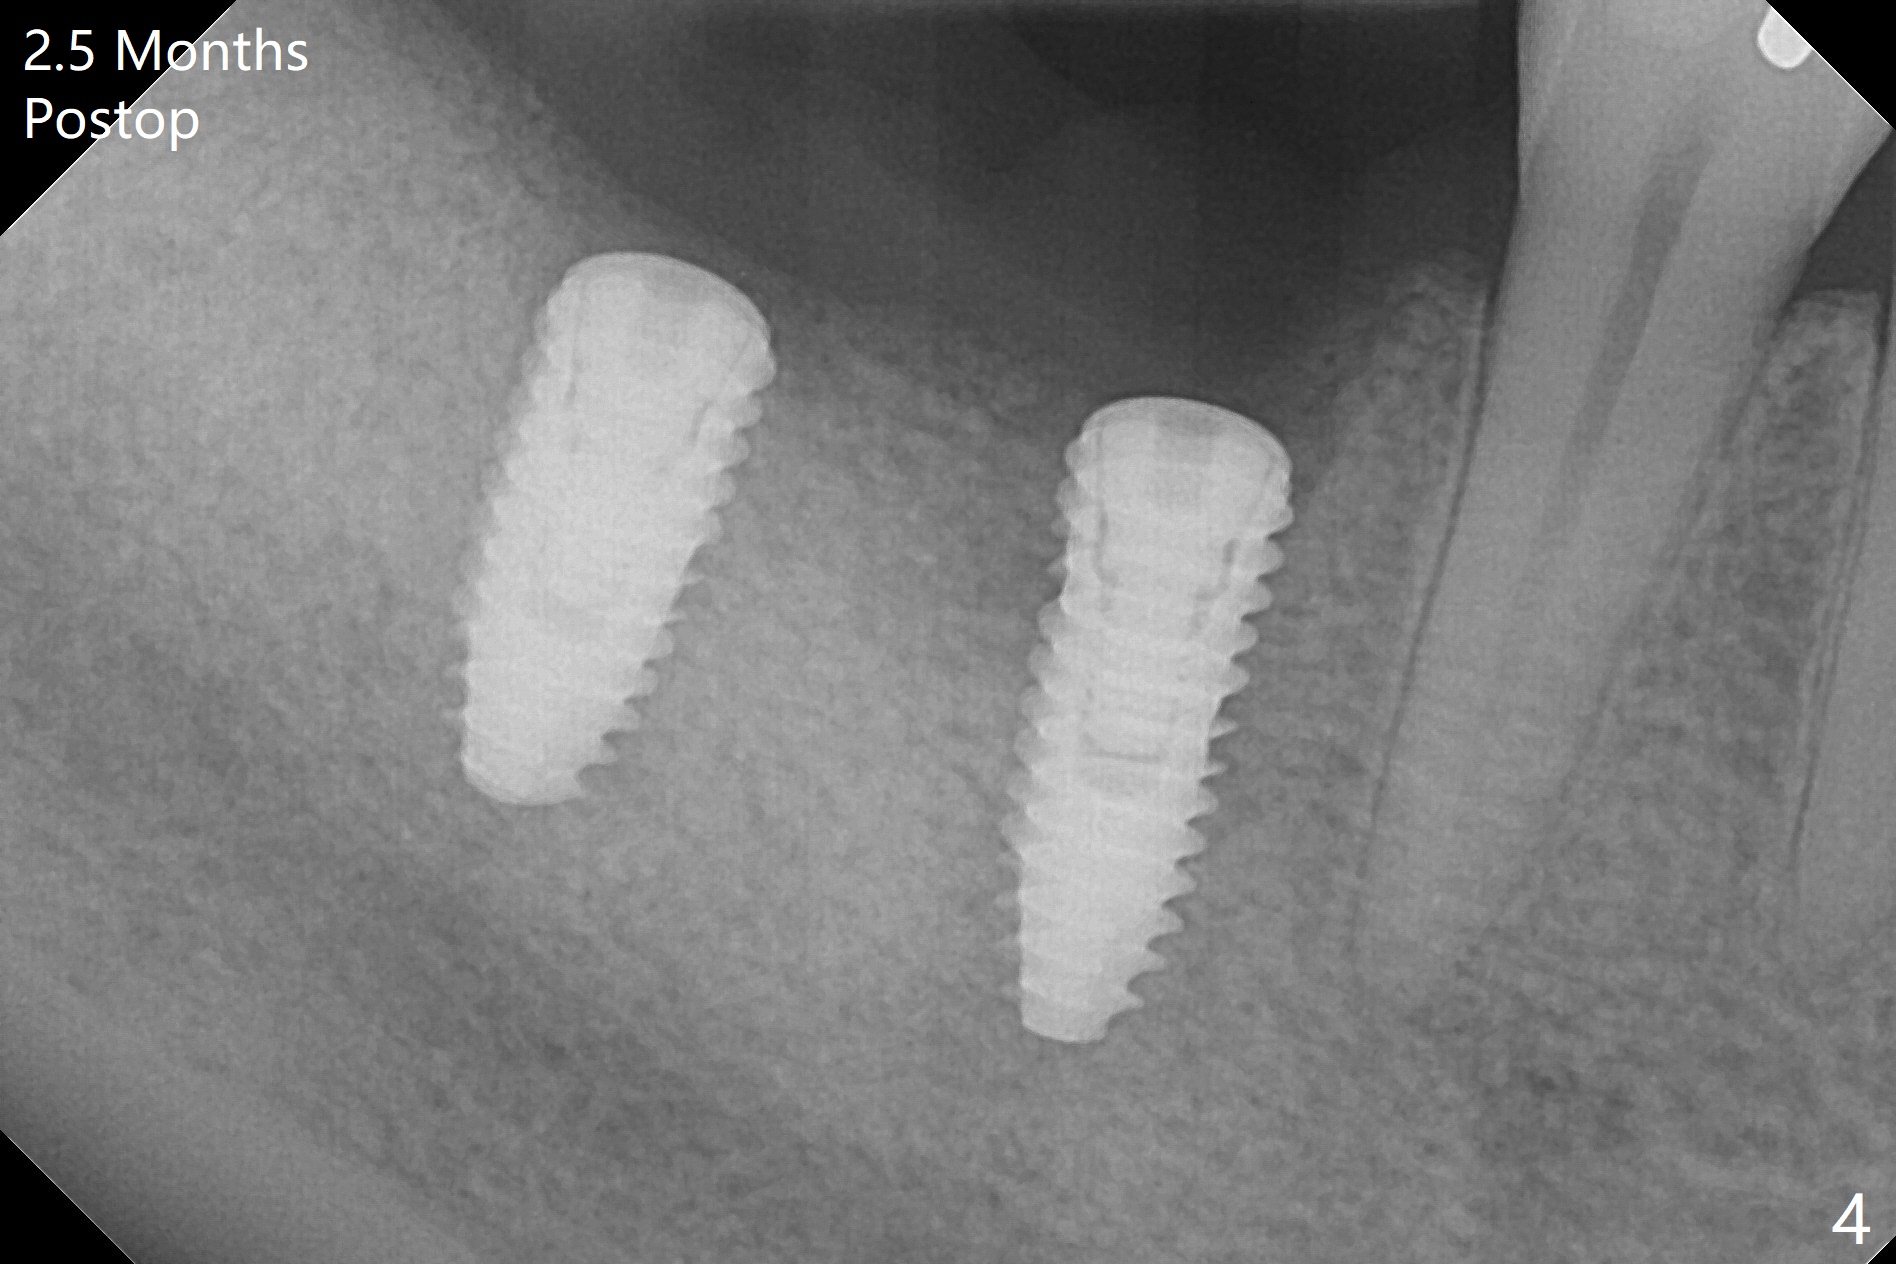

Infection is not so typical.  There is no recent postop X-ray, just 18-19 days postop.   Thanks for the reply.  We will keep watching.  The healing abutments, loose and associated with gingival inflammation, are removed 2.5 months postop (Fig.4).  There is crestal bone resorption, although the implants are stable.  The crestal bone resorption persists especially #30 distal 4 months postop (Fig.5 *).  When the implants are uncovered, there is mild bone loss distobuccal to #30 implant, consistent with early periimplantitis.  Bone graft is placed after debridement and healing abutment placement.  There appears no bone loss nearly 9 months postop (Fig.6).  The soft tissue looks healthy.  Cementation abutments (5.7x4(3) and 5.7x4.5(3) mm at #30,31, respectively) are placed for impression.  The distobuccal gingiva at #30 is hyerplastic 10 months postop (Fig.7 *, immediately before cementation), which is consistent with bone loss (Fig.8,9 * (periimplantitis)).  It is hoped that the infection will dissolve with improved oral hygiene (water pik) over the smooth final restoration.  In fact it is, i.e., the implants at #30 and 31 remain asymptomatic with the healthy gingiva 6 months post cementation (Fig.10,11).  There is mild crestal bone loss at #30 and 31 ten months post cementation (Fig.12).  Crown/implant ratio is the basis for screw loosening.  In fact the crown/abutment at #30 is loose 4 months later.  Incomplete seating of the abutment may be a culprit (Fig.12).  The gingival cuff is not healthy; a 6.8x7 mm healing abutment is placed with gingival blanching with Cetacaine and antibiotic ointment.  Next visit place a new smaller diameter abutment (4.5 or 5.2) with probably longer cuff (4 mm) or the existing abutment with no proximal contact crown, torque 25-30 Ncm and take BW with sensor 2 or PA with sensor 1.  In fact there is resistance to hand tighten a 4.5x4(4) mm healing abutment, which is due to contact with the mesial crest (Fig.13 *).  After use of 5.5 and 6.0 mm profile drills, the 6.8x7 mm healing abutment is reseated.  The latter appears to contact the mesial crest (Fig.14).  Later a 6x5 mm healing abutment is placed.  New crowns with new abutments are delivered 2 years 3 months postop (post Coronavirus lockdown).